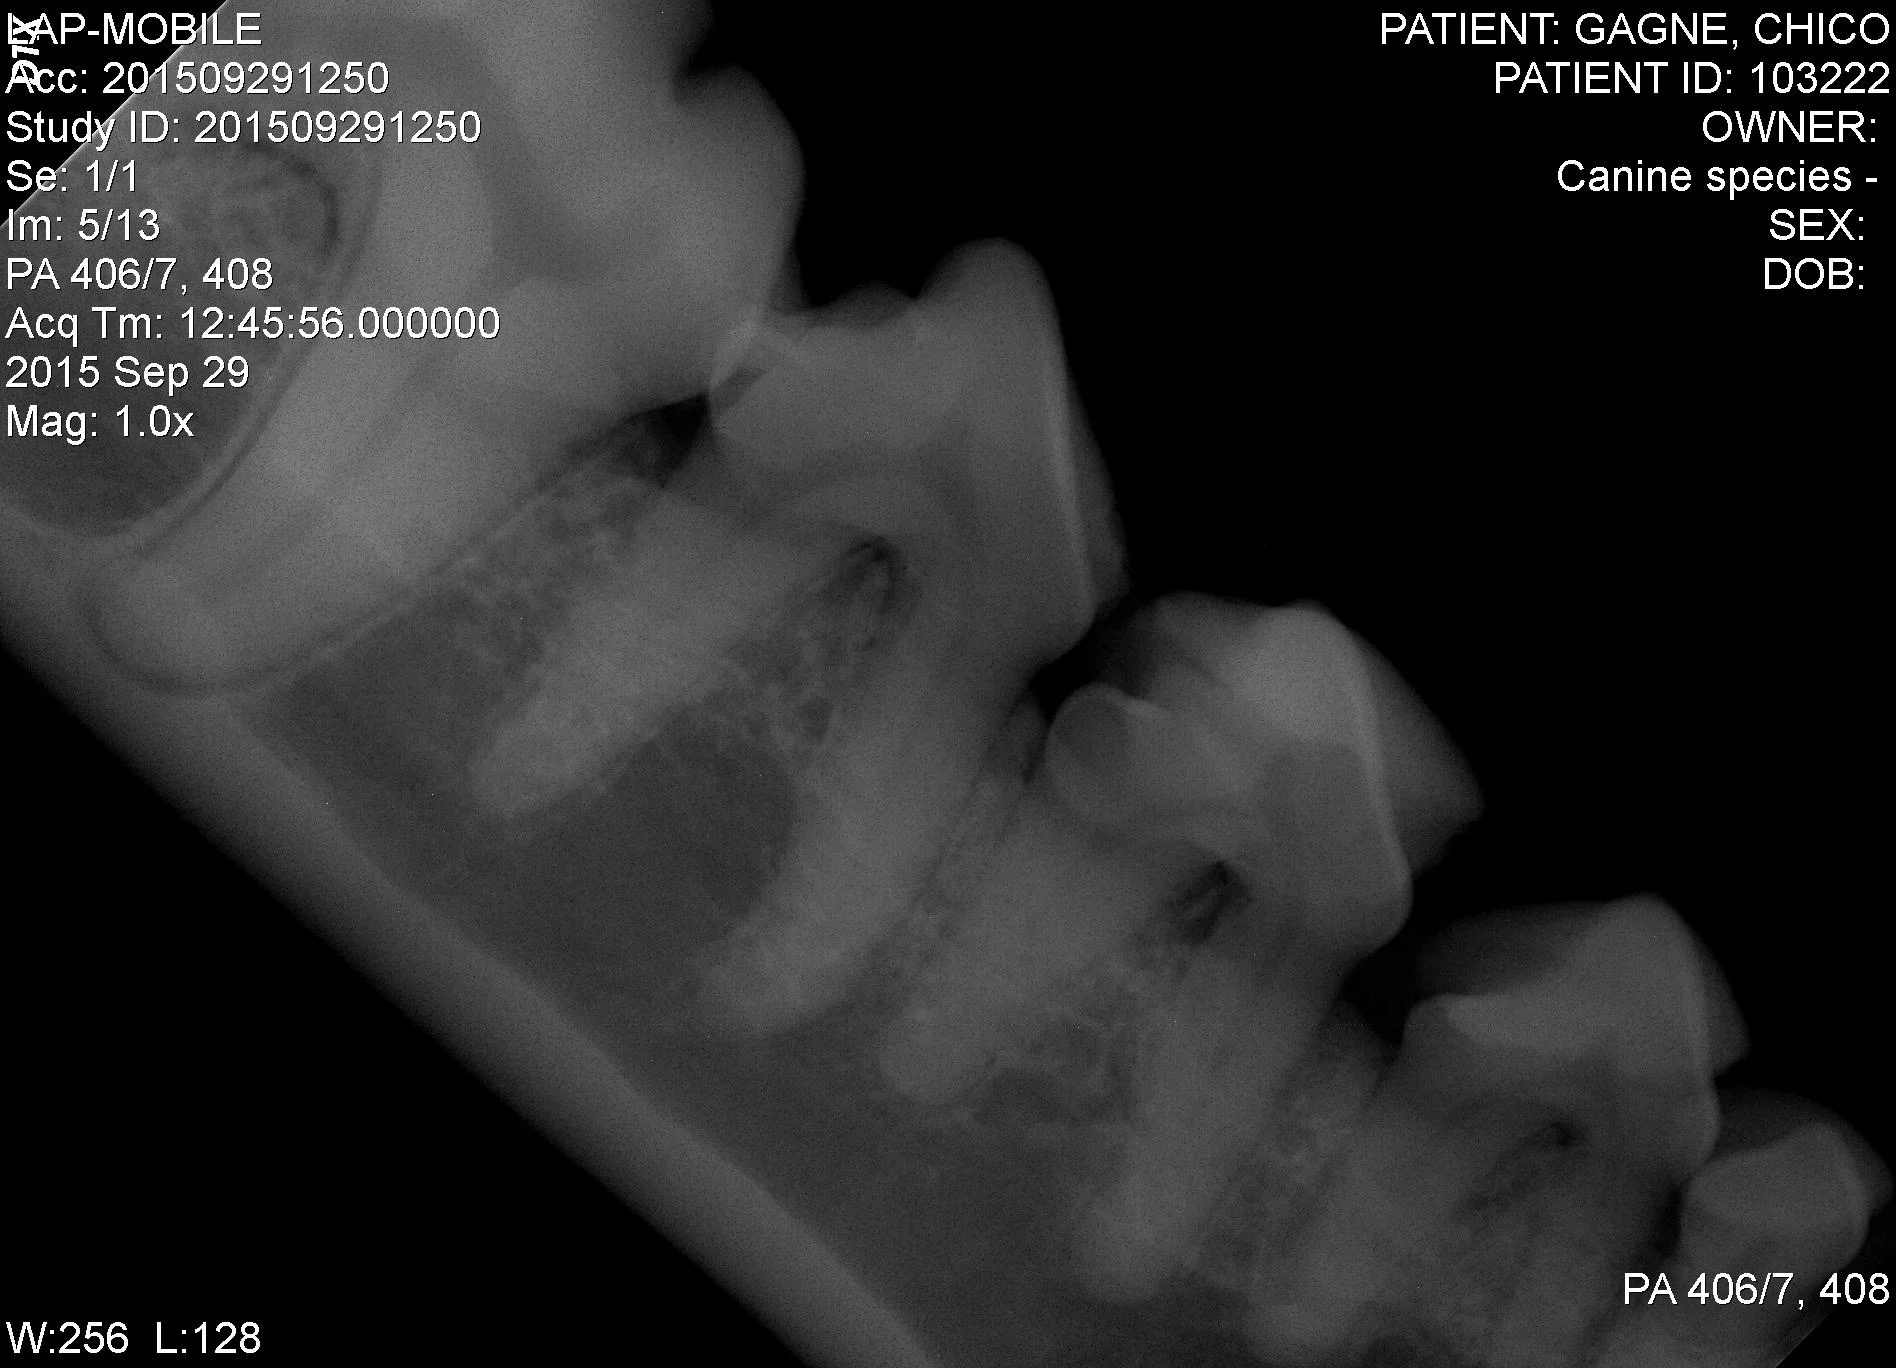

Dental radiography is also available with a small, separate x-ray unit. This unit is designed to take dental x-rays of your pet while he or she is under general anesthetic. This allows the veterinary staff to look for fractured teeth, tooth root abscesses, and cavity-like lesions. It also enables the veterinarian to make important decisions on which teeth need to be monitored more closely during future appointments.